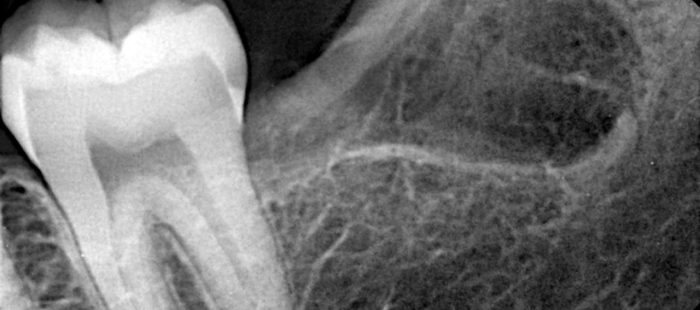

Need a clear and accurate diagnosis for your dental concerns? Our advanced tooth X-ray service in Karachi provides high-resolution digital imaging that helps detect cavities, infections, impacted teeth, bone loss, and hidden dental issues early and precisely.

Many dental issues develop beneath the surface and cannot be seen during a routine exam. Our state-of-the-art tooth X-ray services use high-definition digital radiography to accurately identify cavities, root infections, impacted teeth, periodontal bone loss, and other hidden oral conditions, allowing timely and effective treatment planning. At The Dental Clinic, we combine low-dose digital imaging with strict cross-infection control and international sterilization standards. Every dental radiograph is captured by experienced professionals to ensure optimal image clarity, minimal radiation exposure, and maximum patient safety.

Our advanced digital tooth X-rays deliver sharp, detailed images that help dentists identify problems early and plan treatments with confidence. Patients benefit from faster results and more accurate dental care decisions.

A tooth X-ray is a dental imaging technique that uses low radiation to capture detailed images of teeth, roots, and jawbone. It helps dentists identify cavities, infections, bone loss, and other issues not visible during a routine dental examination.

Dentists recommend tooth X-rays to detect hidden cavities, root infections, bone loss, impacted teeth, and other issues that are not visible during a routine oral examination.